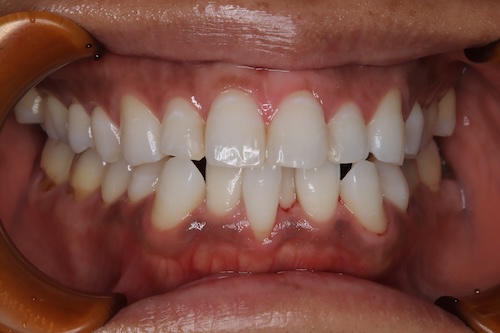

右上1 BL4キープ

右下3 A1キープ

右下3 BL4キープ

シェードにご満足いただいたため、最後にガムピーリングを行いました。歯茎のお色もピンク色になることで、歯のお色がより明るく見えることを期待しています。今後は3ヶ月ごとのクリーニングとホワイトニング、ご自宅ではベリーホワイトとトゥースペーストでのケアを継続していただきます。

お客様の声

ホームホワイトニングをほぼ毎日行ってくださったので、スムーズに白くすることができました。途中、知覚過敏が出ましたが、薬剤のメーカーを変えたり、知覚過敏を抑えるケア商品の使用により、最後までホームホワイトニングを続けることができました。

ステインがつきやすい口腔内環境のため、今後もセルフケアとクリニックでのケアをしっかり継続していくことが大切です。ガムピーリングを行い歯肉の黒ずみを取ることで、歯のお色もさらにトーンアップして映るため、コースの最後にガムピーリングを行うのがおすすめです。